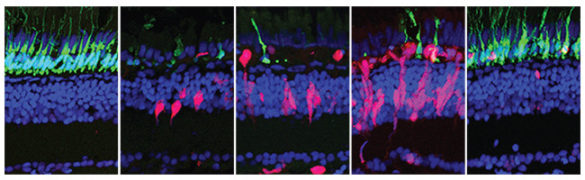

It turns out that the structure of the retinas of fish and mammals are basically the same. Although the retina is very thin – less than 0.5 millimeters thick – it contains three layers of nerve cells: photoreceptors that detect the light, horizontal cells that integrate the signals from the photoreceptors and ganglion cells that receive the visual information and route it to the brain.

In addition, the retina contains a special type of adult stem cell, called Müller glia, that span all three layers and provide mechanical support and electrical insulation. In fish retinas, they also play a key role in regeneration. When regeneration is triggered, the Müller glia dedifferentiate (regress from a specialized state to a simpler state), begin proliferating, and then differentiate into replacements for the damaged nerve cells. Müller glia are also present in mammalian retinas, but don’t regenerate.

They tested their hypothesis in two ways: By blinding zebrafish and injecting them with drugs that stimulate GABA production and by injecting normal zebrafish with an enzyme that lowers the GABA levels in their eyes.

Zebrafish are easily blinded. If they are in total darkness for several days and then exposed to very bright light, all the photoreceptors in their retinas are destroyed. Due to their robust regenerative ability, however, their eyes recover in just 28 days. When the biologists injected drugs that kept GABA concentrations in the retinas of newly blinded fish at a high level, they found that it suppressed the regeneration process.

On the other hand, when they injected an enzyme that lowers GABA levels in the eyes of normal fish, they found that the Müller glia began dedifferentiating and proliferating, the first stage in the regeneration process.

The researchers’ next step is to determine if GABA not only stimulates Müller glia dedifferentiation and proliferation, but also causes the differentiation that produces new photoreceptors and the other specialized neurons in the retina. They are pursuing this in both zebrafish and mice with a grant from the National Eye Institute’s Audacious Goals Initiative.